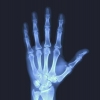

Veja como prevenir a osteoporose e evitar fraturas